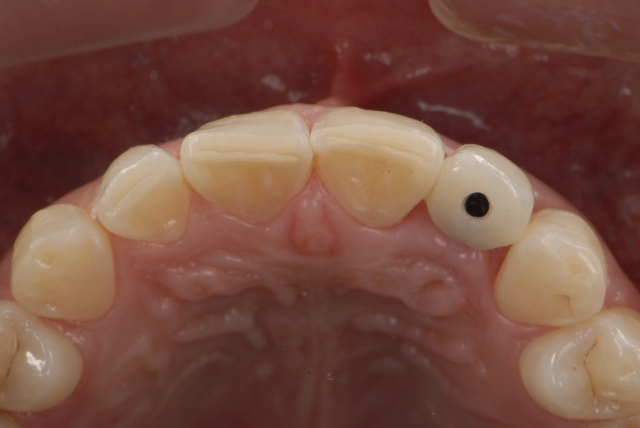

Here is a multi-step process showing the fabrication sequence of a screw-retained single-tooth implant provisional restoration of a lateral incisor.